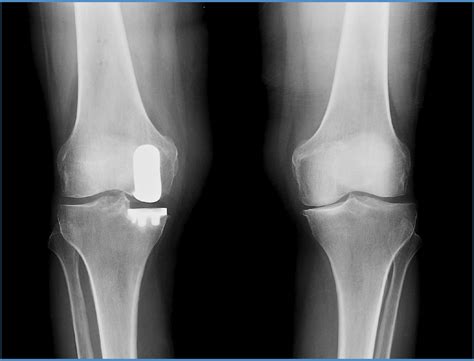

The Mako Knee Replacement is a cutting-edge procedure that utilizes robotic-arm assisted technology to perform partial or total knee replacements. This advanced technology allows surgeons to achieve a higher level of precision and accuracy, resulting in better outcomes for patients. The Mako system uses a 3D CT scan to create a detailed model of the patient's knee, which helps the surgeon plan the surgery with unparalleled accuracy.

Before the surgery, the patient undergoes a 3D CT scan of the affected knee. This scan is used to create a detailed model of the knee, which the surgeon uses to plan the procedure. The surgeon can simulate the surgery on the 3D model, ensuring that the implant will be placed with the highest degree of accuracy.